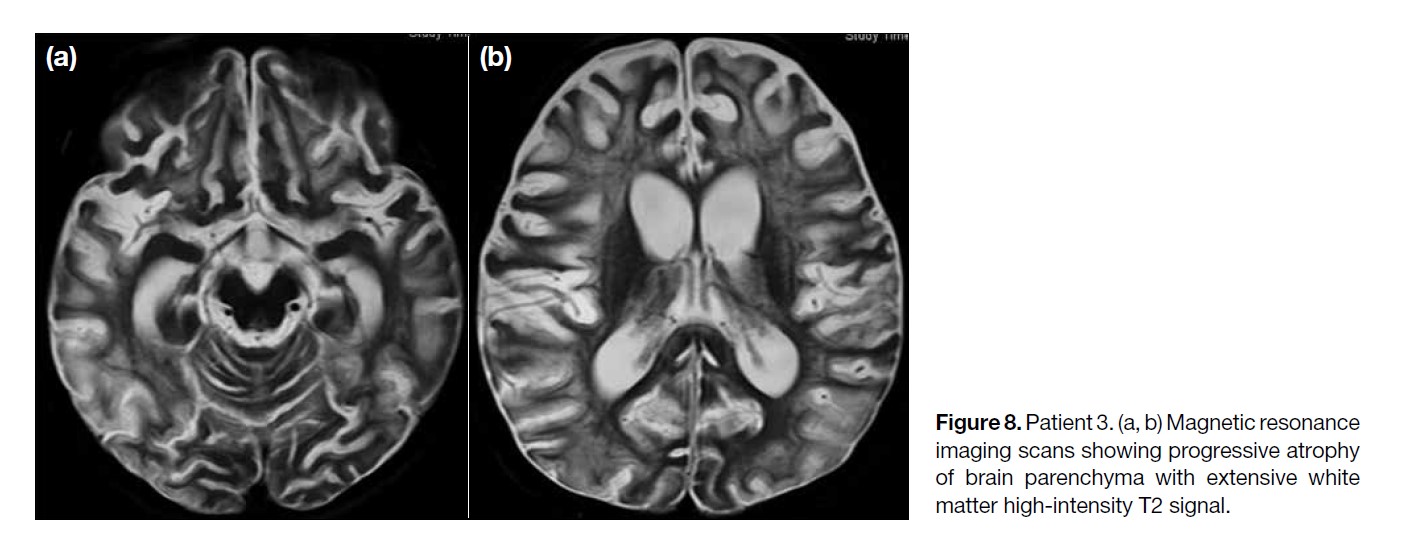

The MRI scan performed 1 month later showed

progressive brain parenchymal loss with extensive

white matter high-intensity T2 signal, also involving the

lentiform nuclei and cerebellum (Figure 8). Progressive

ventriculomegaly was also observed, compatible with

generalised brain parenchymal atrophy.

Figure 8. Patient 3. (a, b) Magnetic resonance

imaging scans showing progressive atrophy

of brain parenchyma with extensive white

matter high-intensity T2 signal.